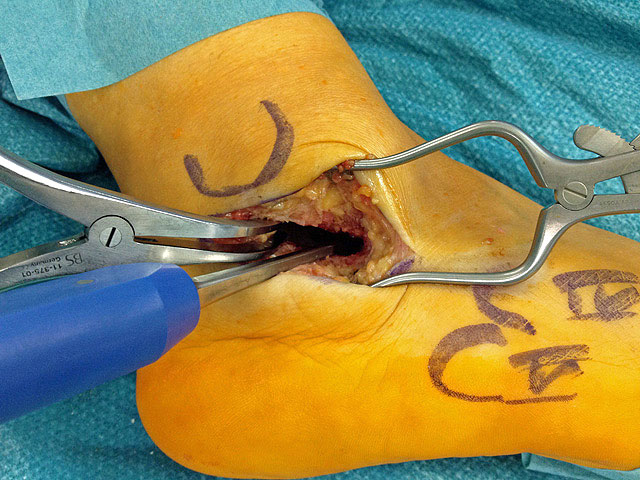

Je nach Operationsziel wird die Arthrodese des Subtalargelenks in verschiedenen Modifikationen durchgeführt. Ist der Rückfuß orthograd ausgerichtet, so erfolgt sie als in situ Fusion, d.h. ohne Korrektur Änderung der Rückfussachse. Liegt eine Rückfuß-Fehlstellung vor, kann diese durch ein additives oder substraktives knöcherndes Vorgehen korrigiert werden 12. Die Fixation der Arthrodese erfolgt üblicherweise mit (kanülierten) Schrauben die über den Tuber calcanei eingebracht werden 3. Eine zweite Schraube zur Sicherung der Rotationsstabilität wird optional über den Processus anterior calcanei im Talushals verankert 4. Der am häufigste verwendete Zugang zum unteren Sprunggelenk verläuft lateral subfibular, alternative Zugänge sind medial oder posterior möglich 56. Ist keine relevante Korrektur notwendig kann der Eingriff auch arthroskopisch durchgeführt werden 78.

Eine Coalitio der medialen Gelenkfacette kann das operative Vorgehen erschweren. Das Gelenk läßt sich nicht öffnen, wird es mit Gewalt aufgehebelt können unkontrollierte Bruchlinien in Kalkaneus und Talus entstehen. Liegt eine Coalitio der medialen Gelenkfacette vor, die meist mit einer Rückfußvalgusstellung vergesellschaftet ist, hat sich ein medialer Zugang bewährt über den die Coalitio reseziert und der Rückfuß in Closing-wedge Technik korrigiert werden kann 1617.